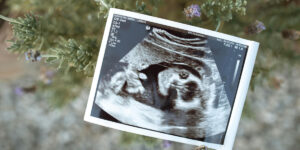

Echo’s tijdens je zwangerschap: wanneer krijg je welke echo?

Wat is een echo precies? Een echo is eigenlijk heel bijzonder: met geluidsgolven maken ze een beeld van je baby, terwijl die lekker in je